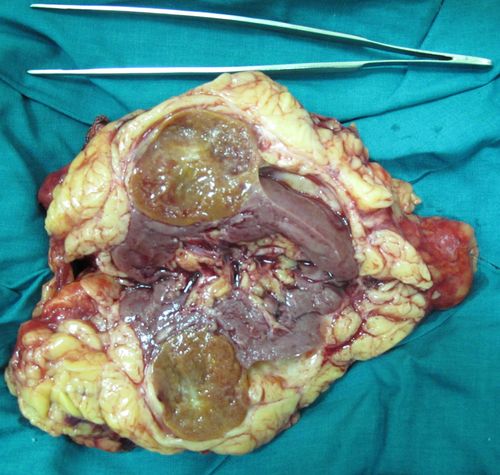

Удаленная почка с опухолью